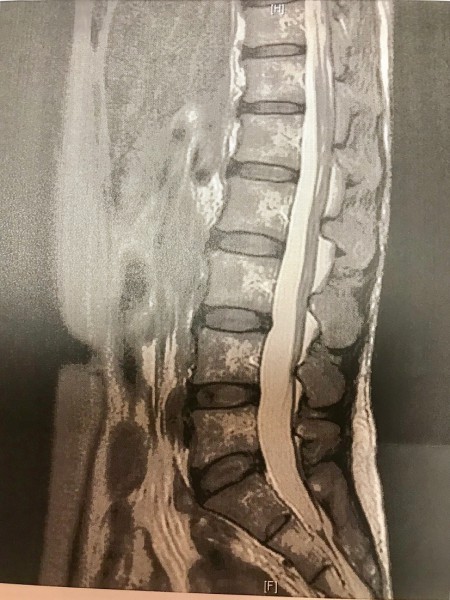

じゃーん。

わたくしの腰の画像です。

『綺麗な腰椎だね。

皮下脂肪も少ないですよ。』とお褒め頂きました。笑